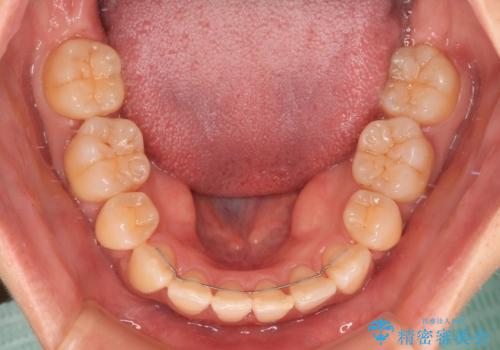

上下前歯の歯軸の角度が大きく改善され、お口を閉じたときに顎先に認められた梅干し様の皺も改善されました。